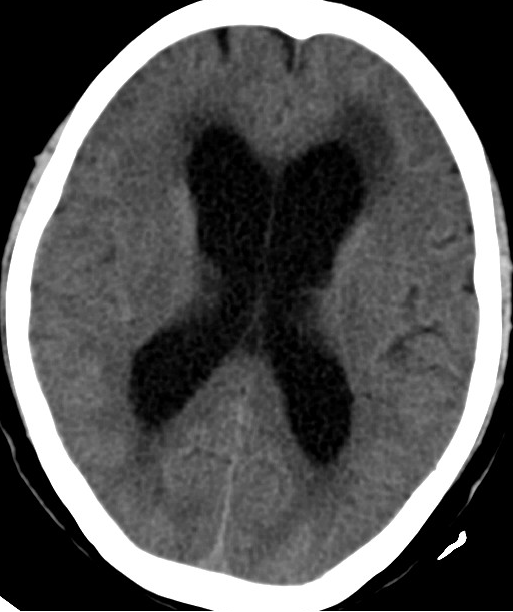

2014-11-28 CT

2015-12-13 MRI

脑积水 OR 颅内静脉血栓?

2013-8-2 CT

腰穿脑压240

2014-10-17 CT

仍时有前额部疼痛,程度轻,调压190—200